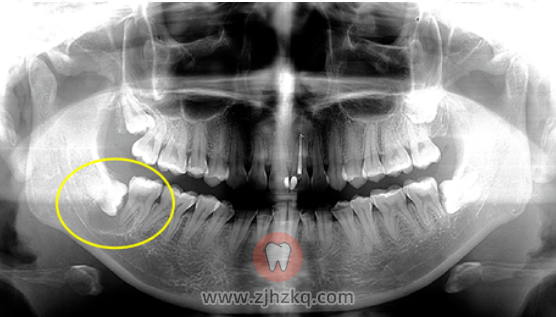

智齿是否一定要拔掉 杭城看牙记 • 2020年8月5日 23:45 • 看牙问答 杭州网友,智齿一定要拔吗? 答:不是所有的智齿都需要拔除。 智齿长得端正,与周围牙齿、牙龈和平共处,还能发挥咀嚼功能;智齿健康,老六或老七英年早逝,老八或许可以作为替补选手上场;智齿安分地待在骨头内,不引起其他病变(但是这种需要定期检查)。 如果智齿长歪了、蛀了、经常发炎,甚至引起囊肿、肿瘤等疾病,比如下面这位,基本注定了其将被拔的命运。 本文内容源自网络仅供参考,不作为诊断医疗依据,更多查询请 → 在线咨询客服